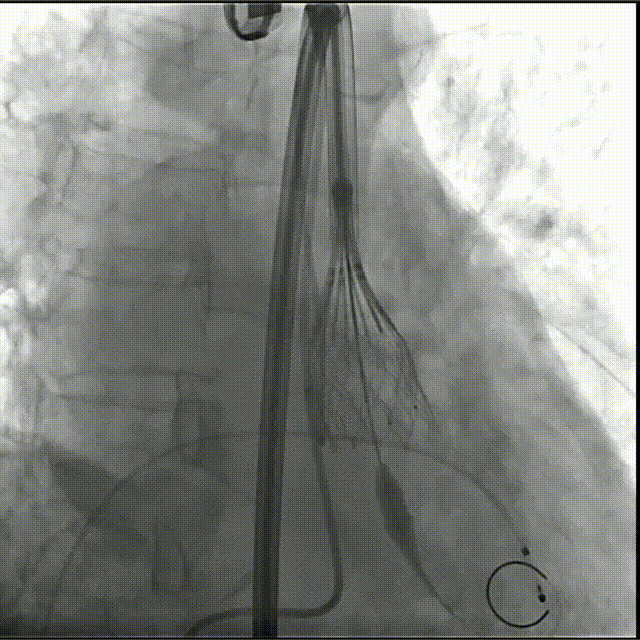

辅入路猪尾根部造影(右窦居中)

瓣膜初始定位

瓣膜开花后造影确认位置

起搏下释放瓣膜至全展开

全展开后造影评估

瓣膜打平造影评估

瓣膜位置可,形态可

脱钩后造影,瓣膜无位移,形态可

弓部剪影,无瓣周漏,升主无损伤